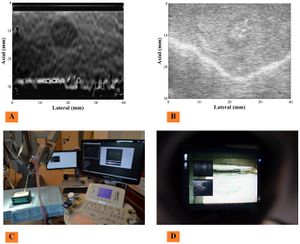

- 4.45 Spinal Curvature Measurement by Tracked Ultrasound Snapshots